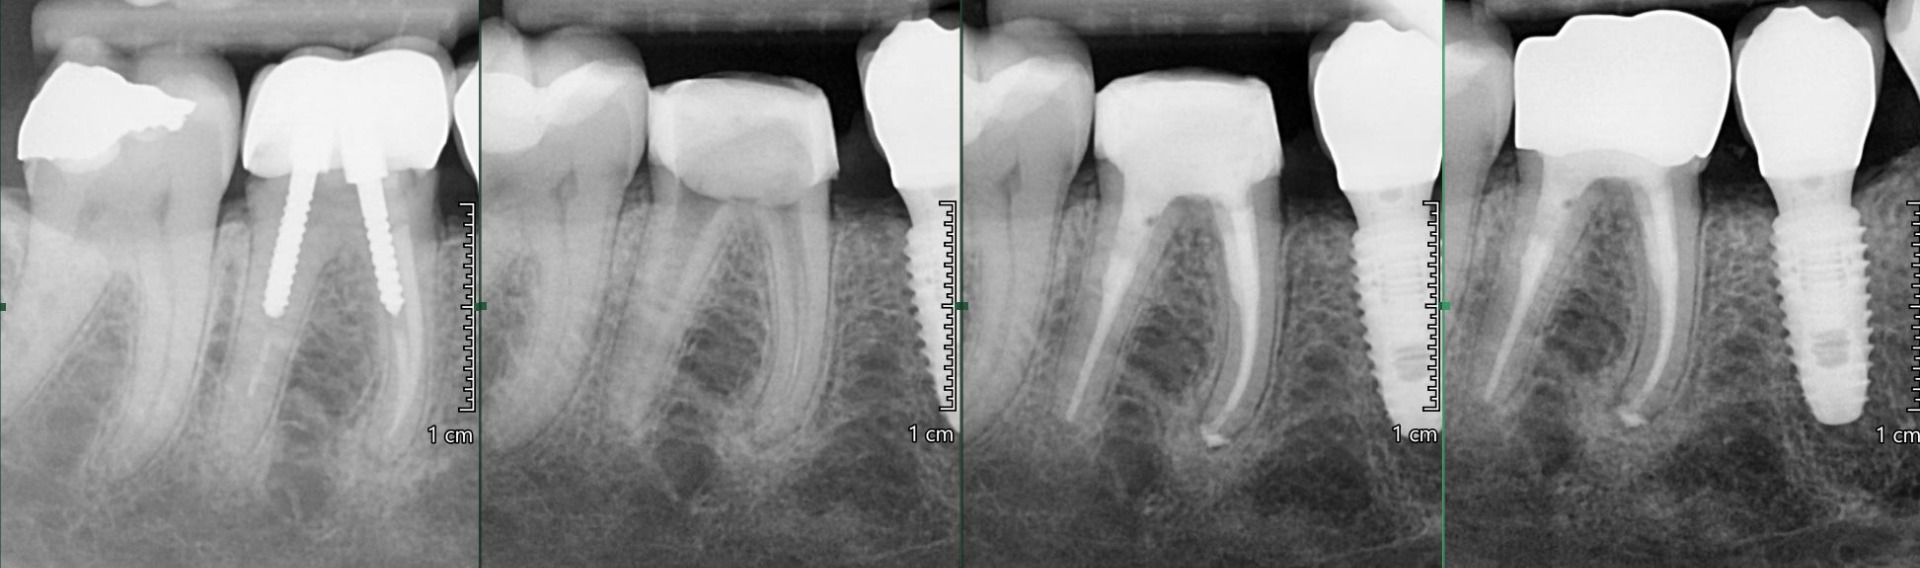

OŠETŘENÍ PACIENTŮ POD OPERAČNÍM MIKROSKOPEM

Nabízíme možnost delegovat Vaše pacienty k (re)endodontickému ošetření pod operačním mikroskopem.